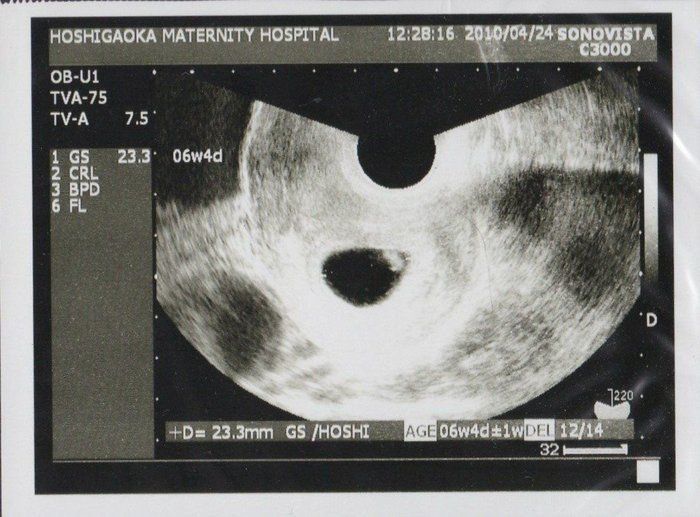

Amiさんの妊娠6週目のエコー写真

初めての健診で、胎嚢の中にいる我が子が確認できました。心拍もしっかりしていたので、医師から「おめでとうございます」と言われ、妊娠が確定しました。まだ23.3mmしかない小さな袋の中の胎芽(妊娠8週未満の赤ちゃんのこと)に、生命誕生の凄さを感じました。